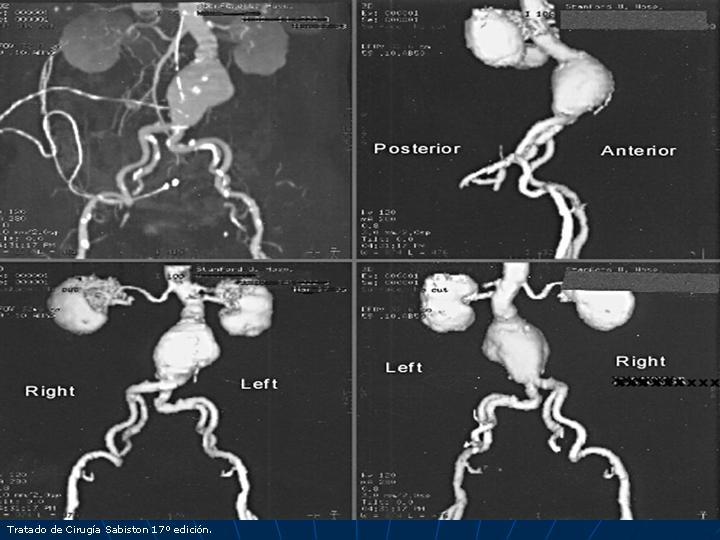

Aneurisma aórtico toracoabdominal (AATA)